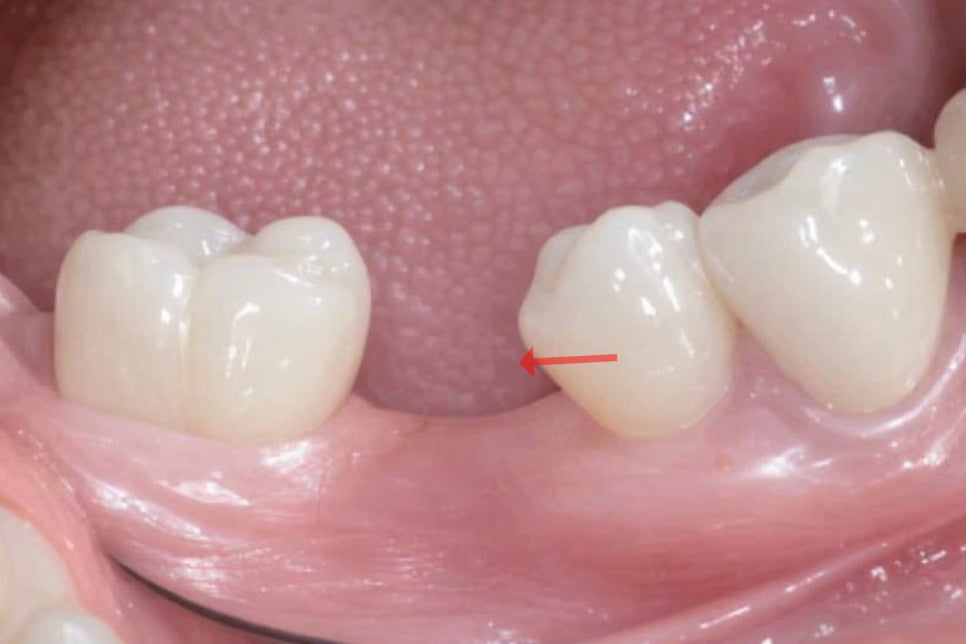

<인접치 이동 및 치열 변화>

치아는 서로 맞물리면서

균형을 이루고 있기 때문에

한 치아가 빠지면 주변 인접치들이

빈 공간으로 서서히 기울어지거나 이동하게 됩니다.

이러한 변화는 치열의 균형을 무너뜨리고

음식물이 더 쉽게 끼게 만들어

우식이나 치주질환의 위험을 높일 수 있습니다.

<반대편 대합치 정출>

위아래로 맞물리던 치아 중 하나가 사라지면

반대편 대합치는 더 이상 저작 시

접촉할 대상이 없어지면서 점차 내려오거나

올라오는 현상이 발생합니다.

이를 정출이라 하며 교합 관계가 흐트러져

저작 기능에 불편감을 일으킬 수 있습니다.